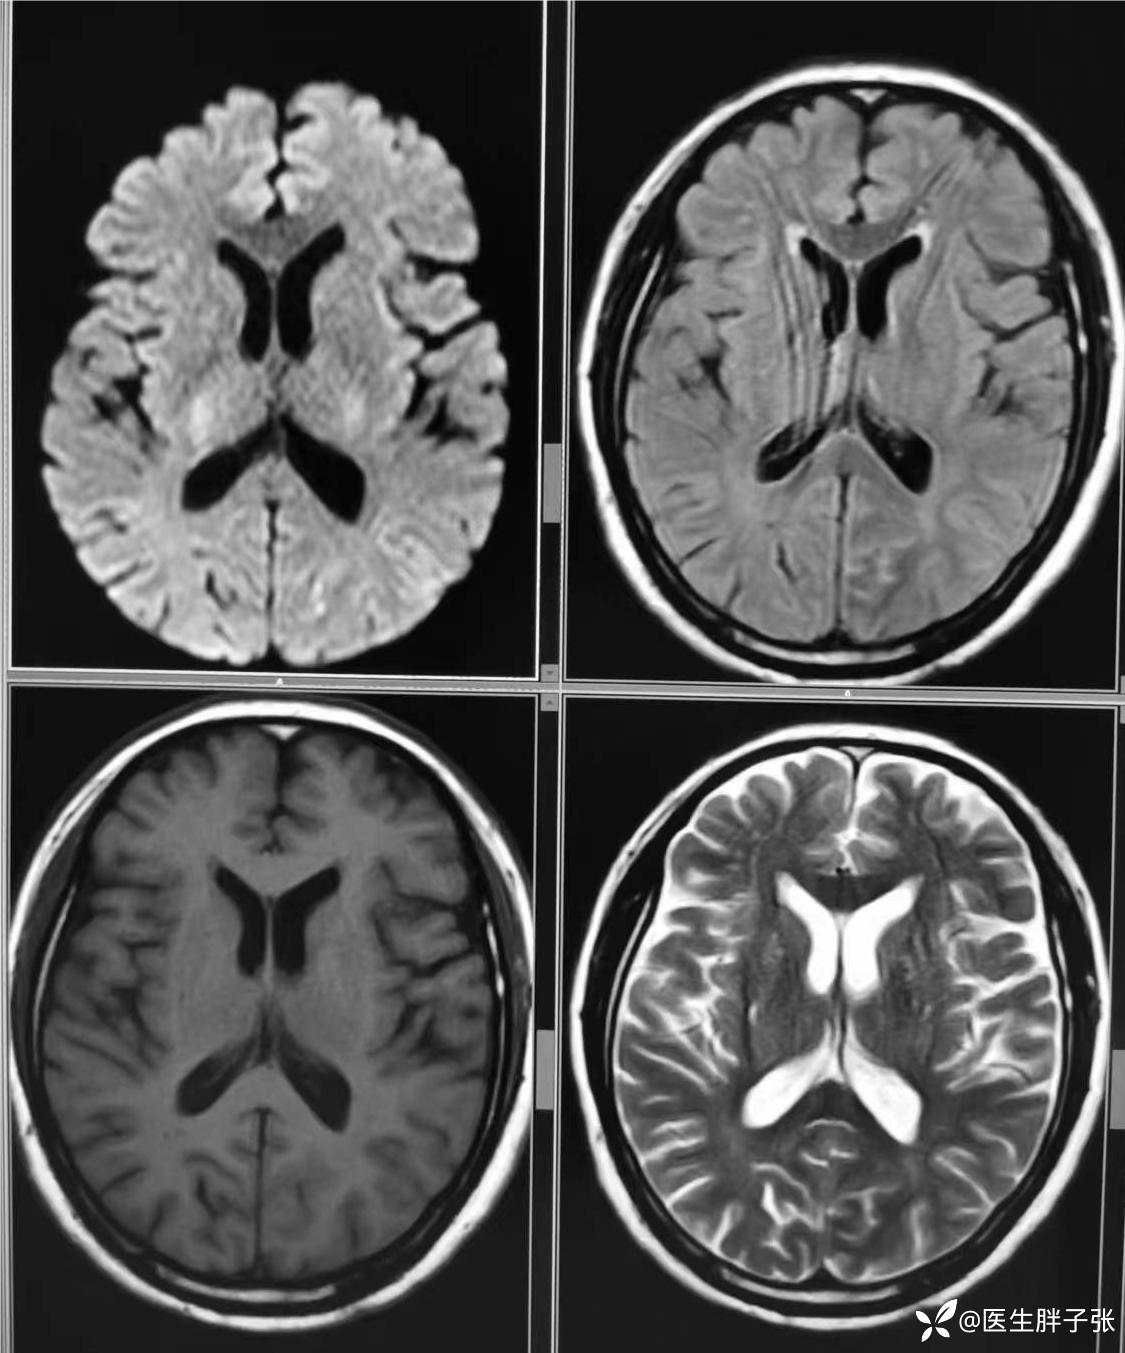

颅脑MR回报左侧顶叶新近梗死灶;多发腔隙性脑梗死及缺血灶;MRA未见异常。

再次查看核磁,考虑患者左侧顶枕叶及右侧枕叶脑组织存在混杂信号。

头颈部CTA提示左侧椎动脉闭塞、右侧椎动脉开口中度狭窄、左侧颈内动脉动脉瘤。

MRV:右侧侧窦纤细,充盈浅淡,上矢状窦后部成窗。